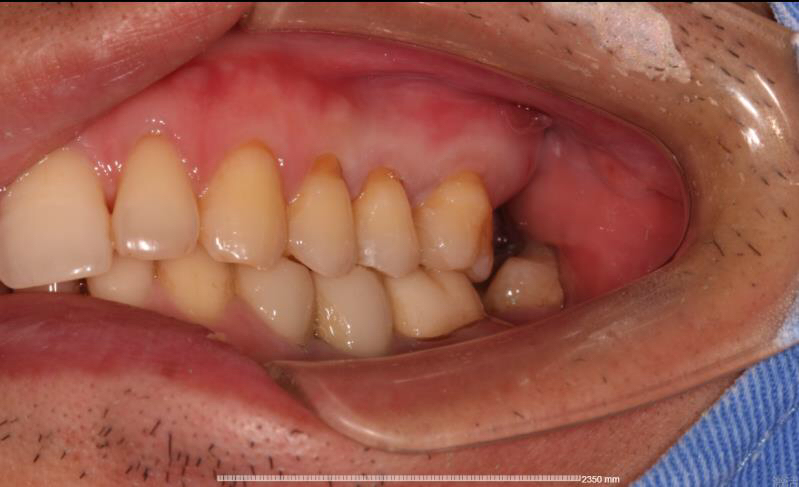

患者中年男性,右上5、6号牙邻接处龋坏,虽然表面没有明显龋坏,但釉质下可见低密度阴影,去龋过程中见釉质下大面积龋坏。由于龋坏面积较大,且位置处在邻接处,传统补牙强度较弱,所以我们建议这位患者采用嵌体修复的方式,一日就诊,一次搞定。